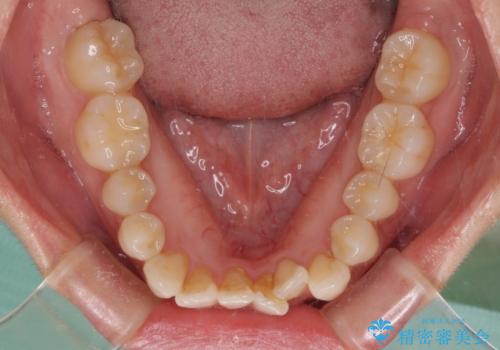

捻れた前歯をできるだけ短期間で 表側のワイヤー矯正

- 上下前歯のねじれを気にして来院された患者様です。

ワイヤー矯正でもマウスピース矯正でも対応可能でしたが、マウスピース矯正の自己管理が面倒であること、上顎前歯の捻転が著しいことから、ワイヤー矯正での治療を希望されました。